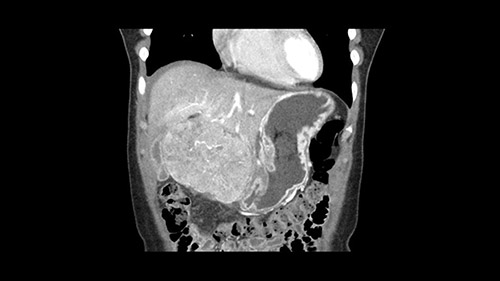

So if we look at the CT scan, on the axial, it’s a larger lesion. It’s about 6 or 7 or 8 centimeters. So it does look a bit threatening in terms of its resectability but if you really drill down deeply into the anatomy, and I think the coronal [imaging] is even better, you can see that the entire mass is on the patient’s left side of the falciform ligament. So it’s really only a left-sided tumor and not even really a left-sided tumor because Segment 4 is uninvolved anatomically.

None of the parenchyma is affected and this tumor is very exophytic; like many Hepatitis B hepatomas; and otherwise is resectable with either a wedge resection part of Segment 2-3 or a formal left lateral segmentectomy.

As I review the CT scan, we have both arterial and venous phases, the tumor is obvious. But I’ll start by saying that the liver itself does not appear to be cirrhotic to my eye. It’s got a normal contour and allied to that, that I do not see evidence of portal hypertension. The spleen is normal, there’s no collateral vessels. The tumor itself, I measured maximally at about 11 centimetres in diameter and I’m told the alpha fetoprotein is very high (over 10000), which is entirely consistent with this being a solitary hepatocellular carcinoma that is very exophytic. It seems to emanate off the inferior margin of Segment 3 (because that’s the falciform). I’ll start by saying that this is not transplantable. The tumor exceeds our guidelines for transplantation, but it's likely resectable based on normal liver and no portal hypertension.

So the issue with regards to resection. A left sided tumor. I believe I can see the falciform ligament right here so we’re looking at a resection of Segments 2, 3 of the left lobe of the liver. The left portal vein is right there. I think we’ll be wiser to take the left portal vein and therefore get well into Segment 4 and do a left hemihepatectomy. Certainly, one does not need to take the middle hepatic vein; it’s miles from the tumor.

Hi my name is Sedat Karademir. I’m from Ankara Guven Hospital and I’m an HPB and transplant surgeon. We are discussing about the case I reviewed the CT of 41 year old lady with a suspected hepatoma in the left lateral segment. Presumably its Segment 3. It looks like a big tumor sitting exophytically mostly out of the liver and pressing on the surrounding organs, but it doesn’t look like any invasion there. In this situation, according to the venous and arterial anatomy, it looks like this will be a Segment 2 and 3 resection.

When you see the axial sections of the scan, you find it's a largely exophytic mass and its well-encapsulated. So this is typically true of a well-differentiated hepatocellular carcinoma. If you look at this, this is the gallbladder which is being displaced to the right and the mass is in the Sg4 of the liver, exophytic, projecting down. As it is coming down, it is also displacing the duodenum and the head of the pancreas which is being pushed towards the left and it's going right up to the cava, the start of the anterior surface of the cava. Obviously getting a lot of collaterals and vascularity from all the vessels around but one has to be very careful in evaluation of the main portal pedicle in this particular case and of course arterial inflow to the Sg4 and of course the left lobe of the liver.

What kind of procedure can we plan for this patient? It obviously has to be a left hemihepatectomy because most of the lesion is actually in Sg4. Can we do something which is less than a hemihepatectomy and just do only a segmental resection? The answer to that is that this vascular supply, if you are trying to ligate only the portal venous pedicle to the Segment 4, it is very close to the tumor and you will end up not having not a great margin as far as tumor resection is concerned so I would recommend a left hemihepatectomy and not just a partial or segmental resection. You can also see that it is crossing the falciform line and going on to Segment 2 and 3 so trying to do anything less than a left hemihepatectomy may not give the right kind of margins which we need for this tumor. Fortunately for us, the contours of the liver, which are very important to see in a Hepatitis B patient, there are no cirrhosis which I can see. The normal liver functions indicate that it's a well compensated Hepatitis B.

My name is Gonzalo Sapisochin. I’m an assistant professor of surgery at the University of Toronto and a hepatobiliary and pancreatic surgical oncologist here at the University Health Network. So this patient has a big mass, likely growing from the left lobe of the liver, around 9-10 cm.

So in planning for this operation, as I look at the scans, I first visualize the arterial phase and I can see that there’s are a lot of big feeding arteries to this large tumor. Likely all the right side vessels feeding the right side of the liver: right hepatic artery and likely the Segment 4 artery are spared from the tumor. It’s likely the left hepatic artery is ramificating and giving feeding arteries to this tumor. It certainly looks like a large mass that its compressing other structures like the cava, the pancreas, the stomach; but I think there’s a plane and we can see that better in the venous phase. There’s a plane of separation between the gallbladder, the pancreas, the cava, that this tumor is abrupting but likely not invading. Usually, these masses actually don’t invade at that level and basically are pushing the tissues and once you open, you’re able to separate the tumor. Sometimes there’s some adhesions but you can actually separate and there’s usually no invasion.

The other thing I would do in this case is to certainly to assess the coronal phase as we can see in the coronal phase, this tumor looks like it's growing from Segment 3, and again I don’t think there’s involvement of the right side of the liver or even on Segment 4.